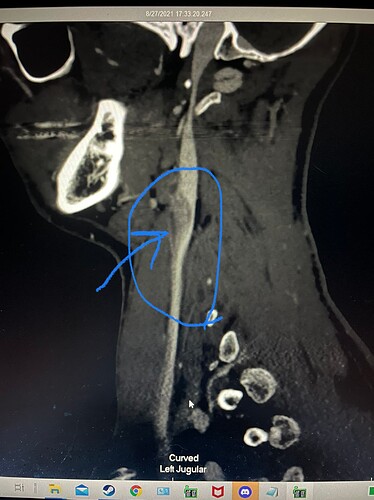

I pointed out a weird dark area near/in my IJV I can’t tell if it’s artifact, clot, or something else compressing it. And I also have a little stenosis on my right lower side of my IJV. If anyone has any info or opinions don’t be scared to let me know.

That is really low, Caleb. Is there any note in your radiology report about the lower stenosis? Any possibility the IJV narrows in that area as a matter of course? The dark area looks like a shadow to me, but best to ask a doctor about it. Shadows shouldn’t show up in CT scans.

Nothing on the report about the stenosis, also I think the dark spot is some kind of artifact